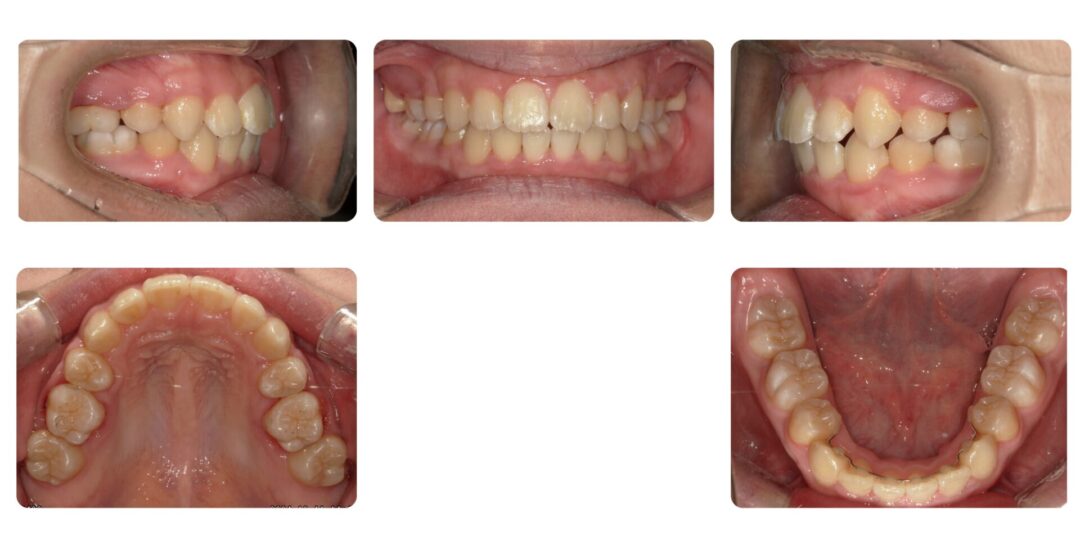

下顎前歯部重度叢生を伴う骨格性上顎前突|初診時13歳

矯正治療後

第二期治療 上下左右4番抜歯 マルチブラケット装置による歯列矯正

2年11ヶ月